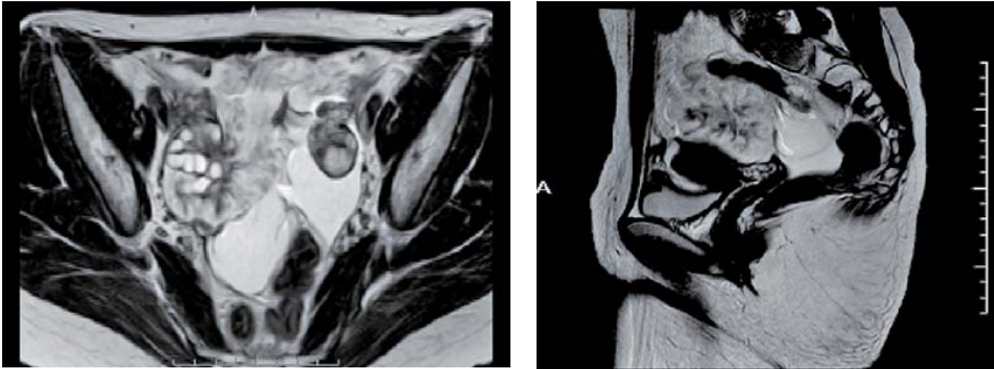

MRI:

両側卵巣に嚢胞構造(T2WI高信号、T1WI軽度低信号)

骨盤底部、右付属器表面に付着する腫瘤

明瞭なT2WI高信号、T1WI低信号、DWI高信号、ADC高値

右卵巣表面に連なるT2WI低信号の樹枝状構造

樹枝状構造は造影され、腫瘤本体は造影効果が弱い

少量の腹水と軽度腹膜肥厚

右卵巣より外向性に発育するカリフラワー状の腫瘤